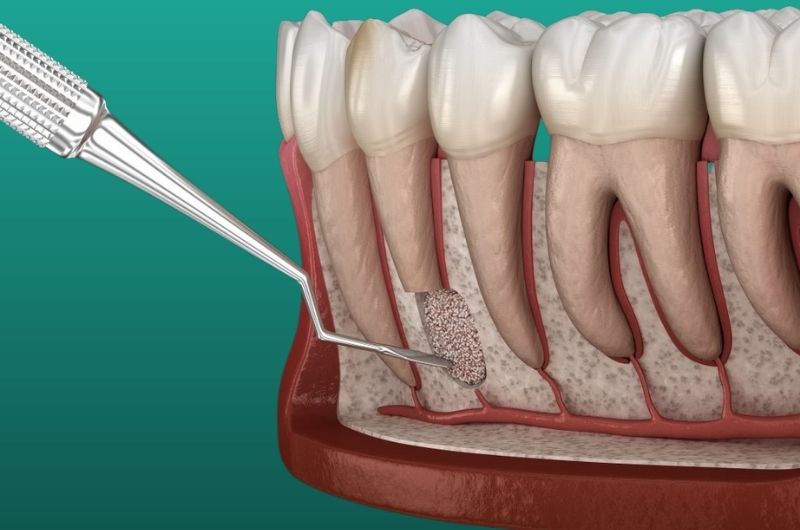

- Bizonyos esetekben gyógyszeres tömés alkalmazása szükséges (ún. retrográd gyökértömés) a gyökércsatorna résmentes lezárására a csúcsi részen